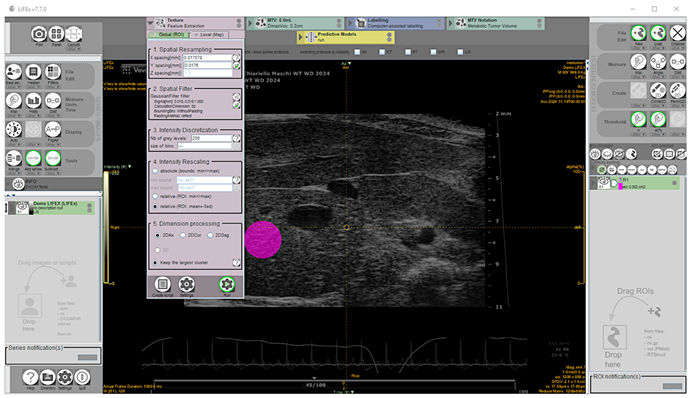

39]. A total of 135 images, including 87 from mice diagnosed for hepatic steatosis of any degree on histology, and 48 from mice for which the disease was excluded, were analyzed offline. The texture feature extraction from HFUS images was performed using the open-source application LIFEx v7.7.0 (LITO, Curie, Iserm, CNRS, Paris-Sud, University Paris Saclay, Orsay. Download available from 18 November 2024) [

40]. Proprietary file formats were converted to the Digital Imaging and Communications in Medicine (DICOM) format and stored in a digital image archive. The workflow of the proposed CAD scheme consisted of the following steps: (1) image selection; (2) liver segmentation; (3) image pre-processing; (4) feature extraction; (5) feature selection. Briefly, a complete set of HFUS images in DICOM format was loaded into the Graphical User Interface (GUI), then one HFUS image was selected for each scanned liver lobe at a defined time point, representing the best frame in the cine loop (according to the criteria described above). To perform segmentation, a single-stack image series must be saved from RGB color recorded layers as active reference using the “save series” tool (format: DICOM; size: 2D) and the chosen frame loaded. To ensure consistency and reliable statistics, a 100-voxel circular region of interest (ROI) was manually placed on the liver parenchyma in the focal area as close as possible to the image center to minimize echo distortion artifacts, avoiding vascular or biliary system structures. [

41]. Subsequently, a low pass 2D Gaussian filter was applied to the ROI images for speckle noise reduction and feature repeatability improvement (kernel: X, Y = 0.018 mm; padding method: reflect, on the exact bounding box of the activated ROI without additional padding) [

14,

42,

43]. Before texture analysis, signal intensity in the ROI was corrected by the mean and three standard deviations to minimize overall grayscale variation between images and scanners [

41]. Then, texture-related features were computed (spatial resampling: x-spacing = 0.017578 mm, y-spacing = 0.0176 mm; intensity discretization ROI drawn: N. Gray Level = 256; bin size = 0.30; intensity rescaling: relative) [

43,

44] (

Figure 2).